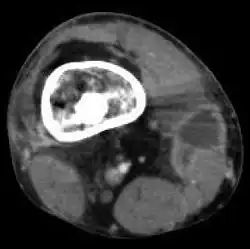

| Osteomyelitis of the 1st toe | |